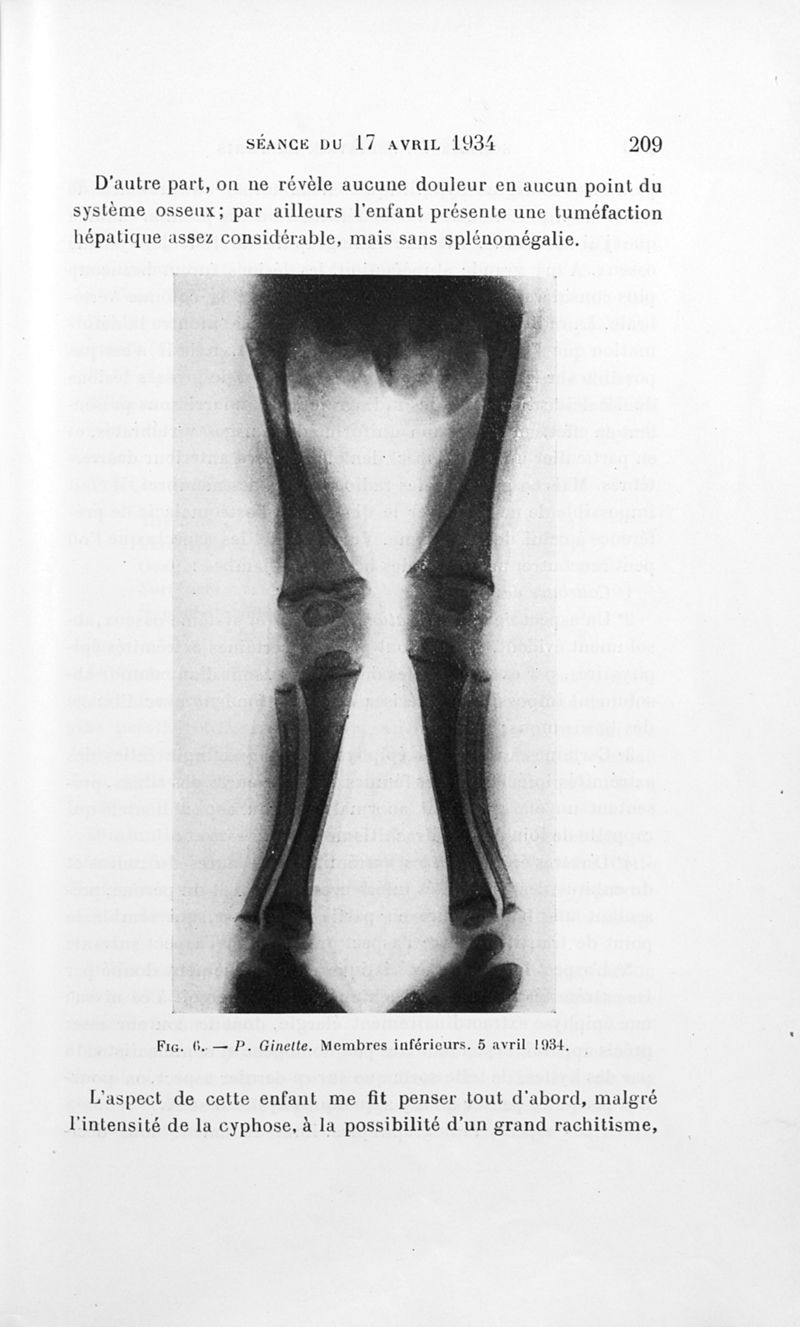

Bulletins de la société de pédiatrie de Paris

Tome trente-deuxième. - Paris : Masson et Cie, 1934.